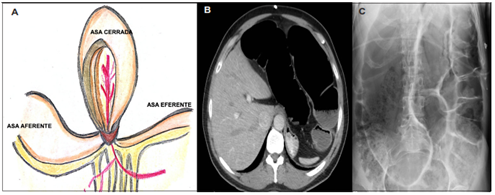

En la Figura 2 se muestran algunos ejemplos de los posibles hallazgos en la tomografía abdominal. La identificación en la TC de una zona de transición es de vital importancia como un indicador de manejo quirúrgico, asociado a una ingurgitación de venas mesentéricas, el espesor de la pared intestinal mayor de 3 mm, la presencia de neumatosis intestinal, el edema mesentérico, el líquido libre intraabdominal y el gas en la vena mesentérica o porta, entre otros 10,11. Estos signos imagenológicos se resumen en la Figura 3.

Figura 2. A-B. Dilatación de las asas intestinales delgadas con una zona de transición en el íleon terminal en la pelvis compatible con obstrucción mecánica. C. Distensión del ciego y colon ascendente con neumatosis y edema mesentérico asociado D. Tomografía de abdomen con evidencia de líquido libre.